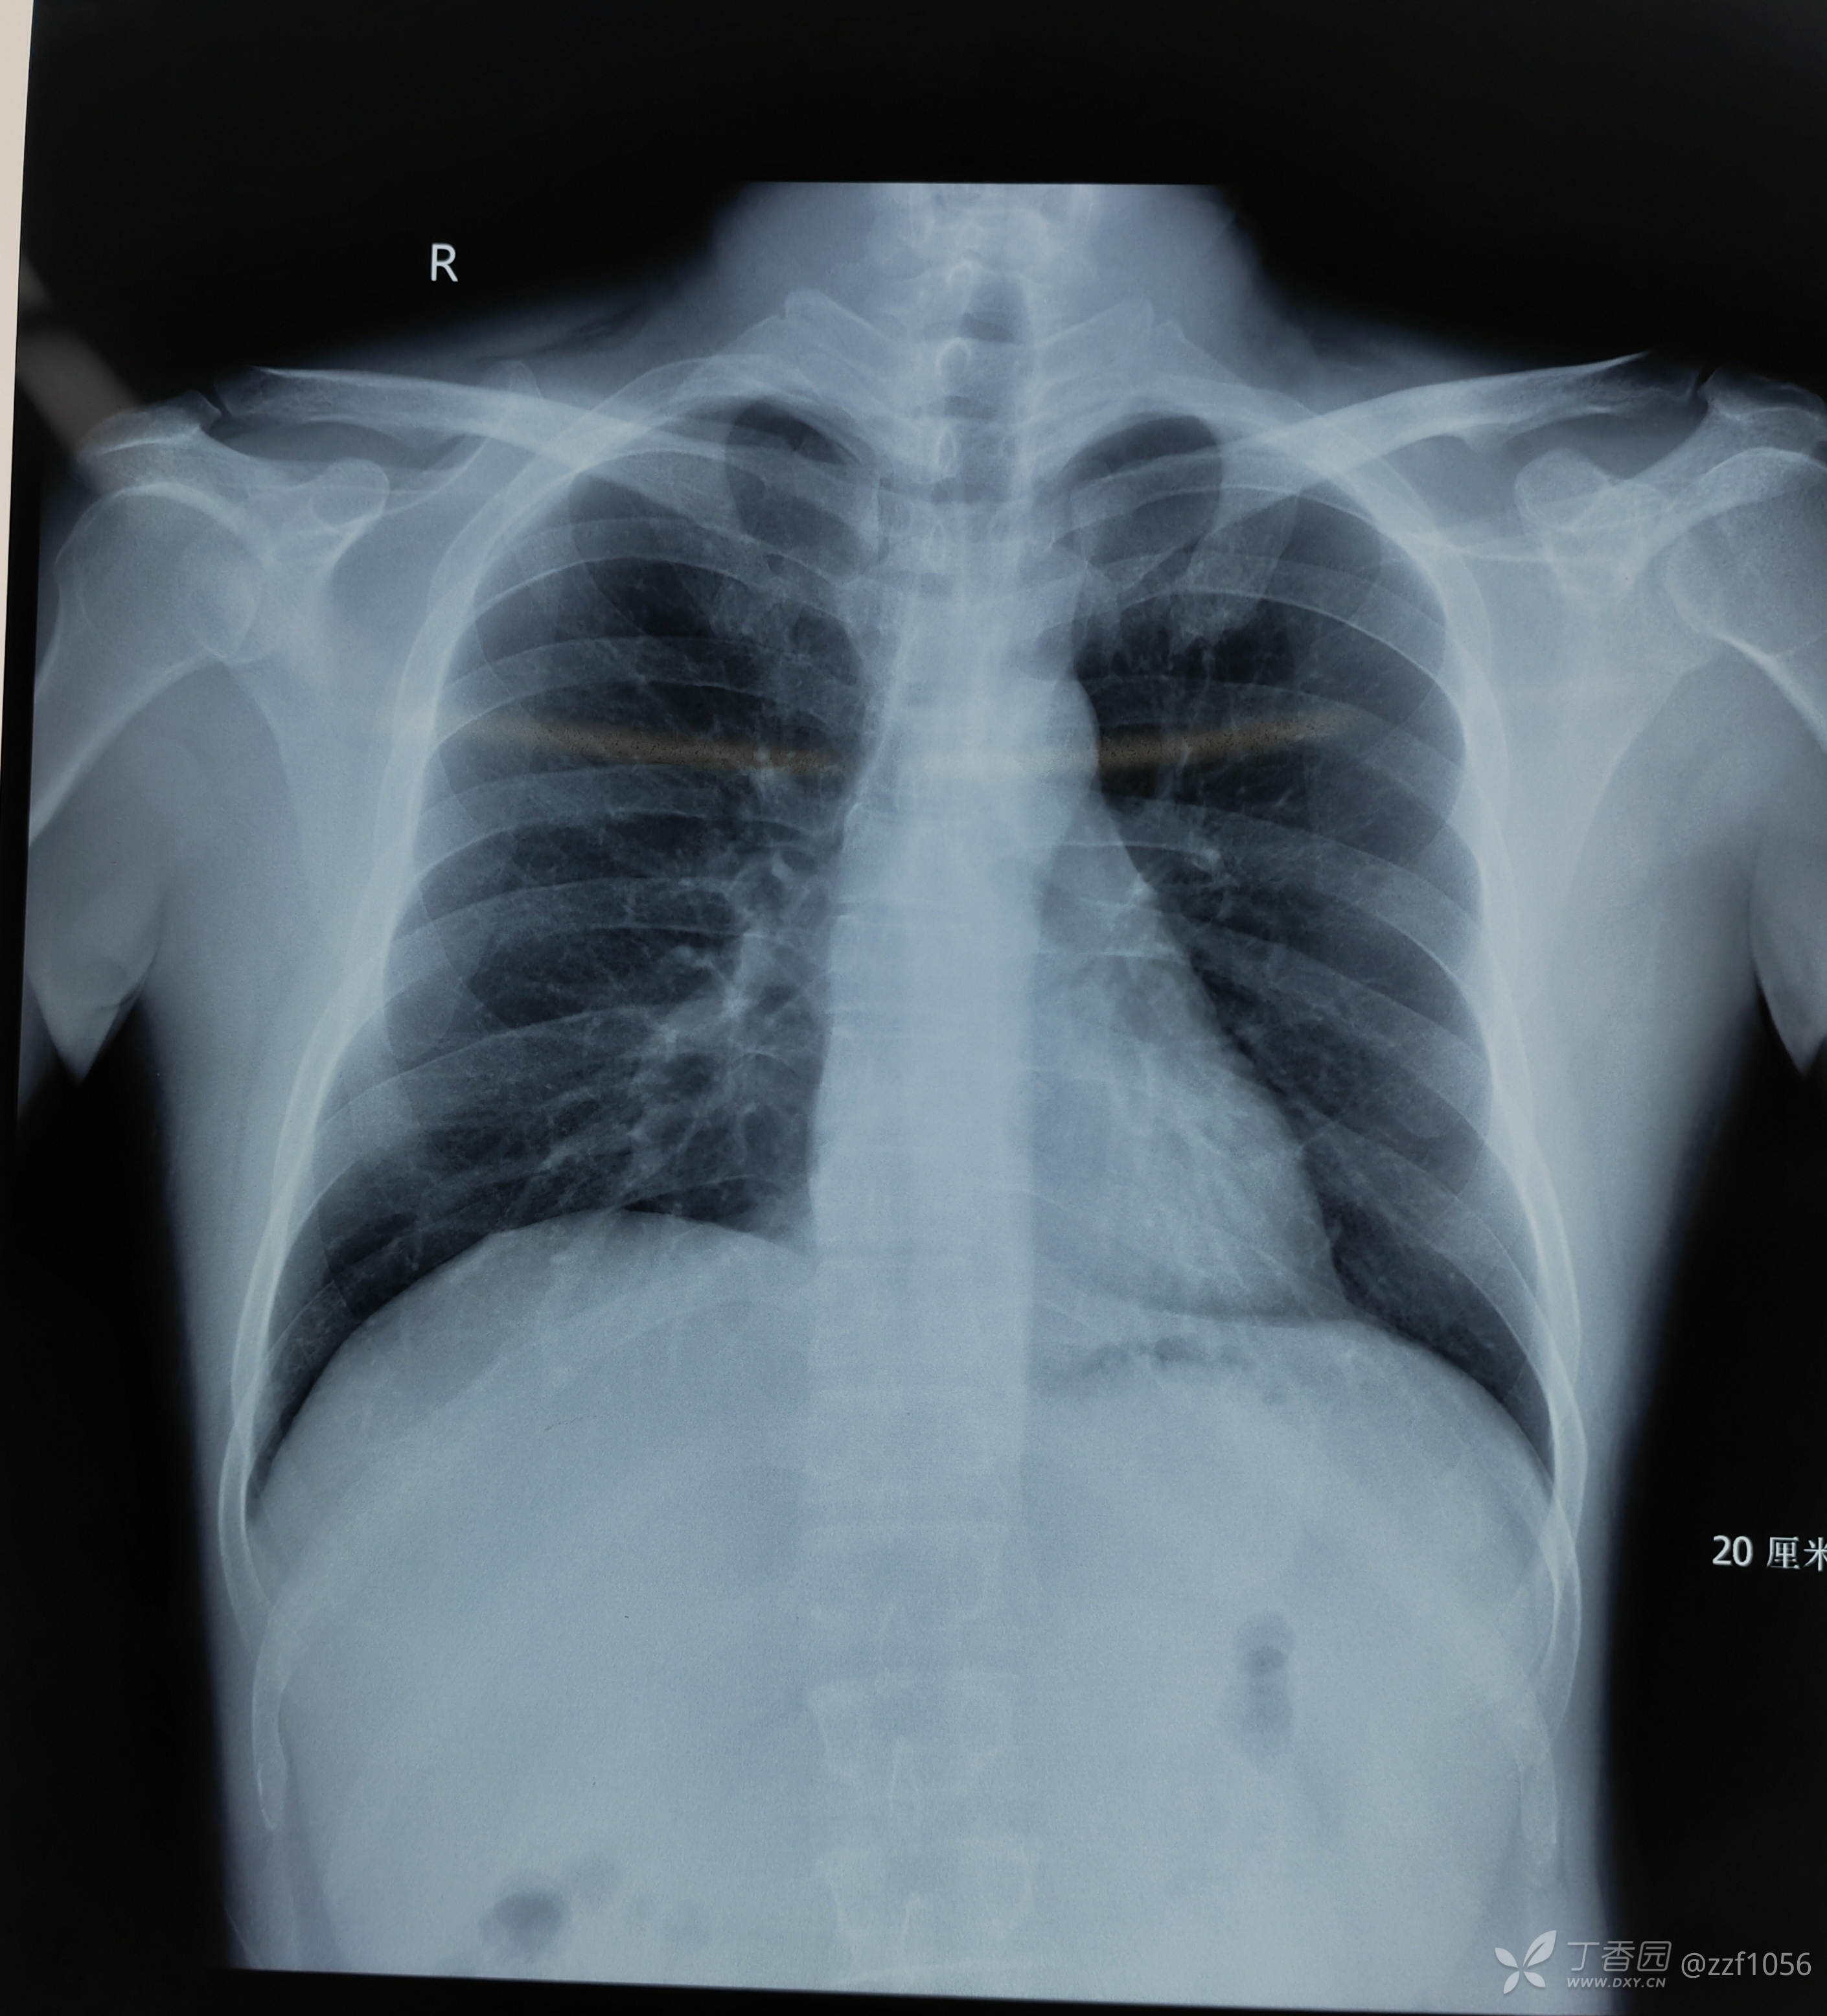

LDH孔镜复发还是扭伤所致?肋骨少一根还是多一根?

huang_zhe_yuan 推荐患者男35岁,腰腿痛一月。

诊断LDH(L5/S1)

两年半以前曾做过椎间孔镜,术后效果好,后经常长时间开车,自诉经常闪腰

先睹影像

肋骨够数吗?

L1还是T12,三长四短五肥大